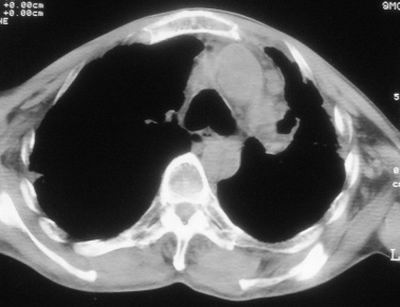

标题: CT11864:男,47岁,反复咳嗽、咯痰、咯血3年,请分析. [打印本页]

患者,男,47岁,反复咳嗽、咯痰、咯血3年,再发5天。痰培养未找到真菌、抗酸杆菌、癌细胞。

左肺上叶体积明显缩小,其内见多发透光区,纵隔向左侧移位,左肺下叶多发班片状病灶,边界模糊,1左肺上叶先天肺发育不全,2左肺下叶肺炎,

左肺上叶结核伴肺纤维化,纵隔移位,左肺下叶感染性病变,建议抗炎抗结核后复查,双肺气肿.

以下是引用xulianj在2008-2-25 21:01:00的发言:[br]左肺上叶结核伴肺纤维化有霉菌球形成,纵隔移位,左肺下叶感染性病变,建议抗炎抗结核后复查,双肺气肿.

考虑:左肺慢纤伴霉菌球形成、双肺全小叶型肺气肿。

1)考虑为:左肺上叶肺结核(空洞形成),伴左下肺感染;不排除霉菌感染可能。2)肺气肿。

左肺上叶结核伴肺纤维化空洞形成并左肺下叶感染,纵隔牵拉移位,建议作进一步检查排除左侧肺霉菌感染可能。